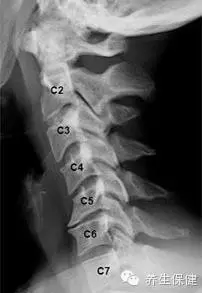

怎樣才能知道自己的頸椎是否健康?日常生活中身體發出的小信號會提示不同類型的頸椎問題。

號一:長時低頭伏案工作,感覺到頭暈難受,考慮為椎動脈型頸椎病;

信號二:不明原因的肩頸痠痛,手臂發麻,考慮為神經根型頸椎病;

信號三:正常直行走路卻常出現「跑偏」問題,考慮為脊髓型頸椎病;

信號四:經常有不明原因的頭暈、眼花、耳鳴、手麻、心動過速、心前區疼痛等一係列症狀,考慮為交感神經型頸椎病。

如果同時出現上述幾類症狀,則考慮為混合型頸椎病。